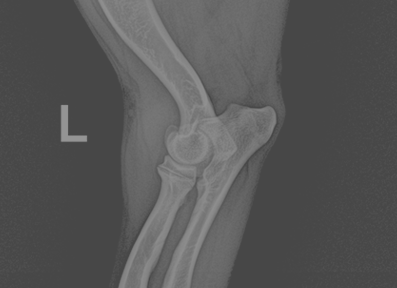

슬개골 탈구 (Patellar Luxation)

슬개골 탈구는 무릎관전의 해부학적 정렬 이상으로 인해 보행장애와 만성 통증을 유발합니다. 본원에서는 정밀한 보행 분석과 촉진, X-ray 및 필요 시 CT 기반의 골격 정렬 평가를 통해 탈구의 위치와 정도, 주변 연부조직과 골 변형 여부를 종합적으로 판단합니다.